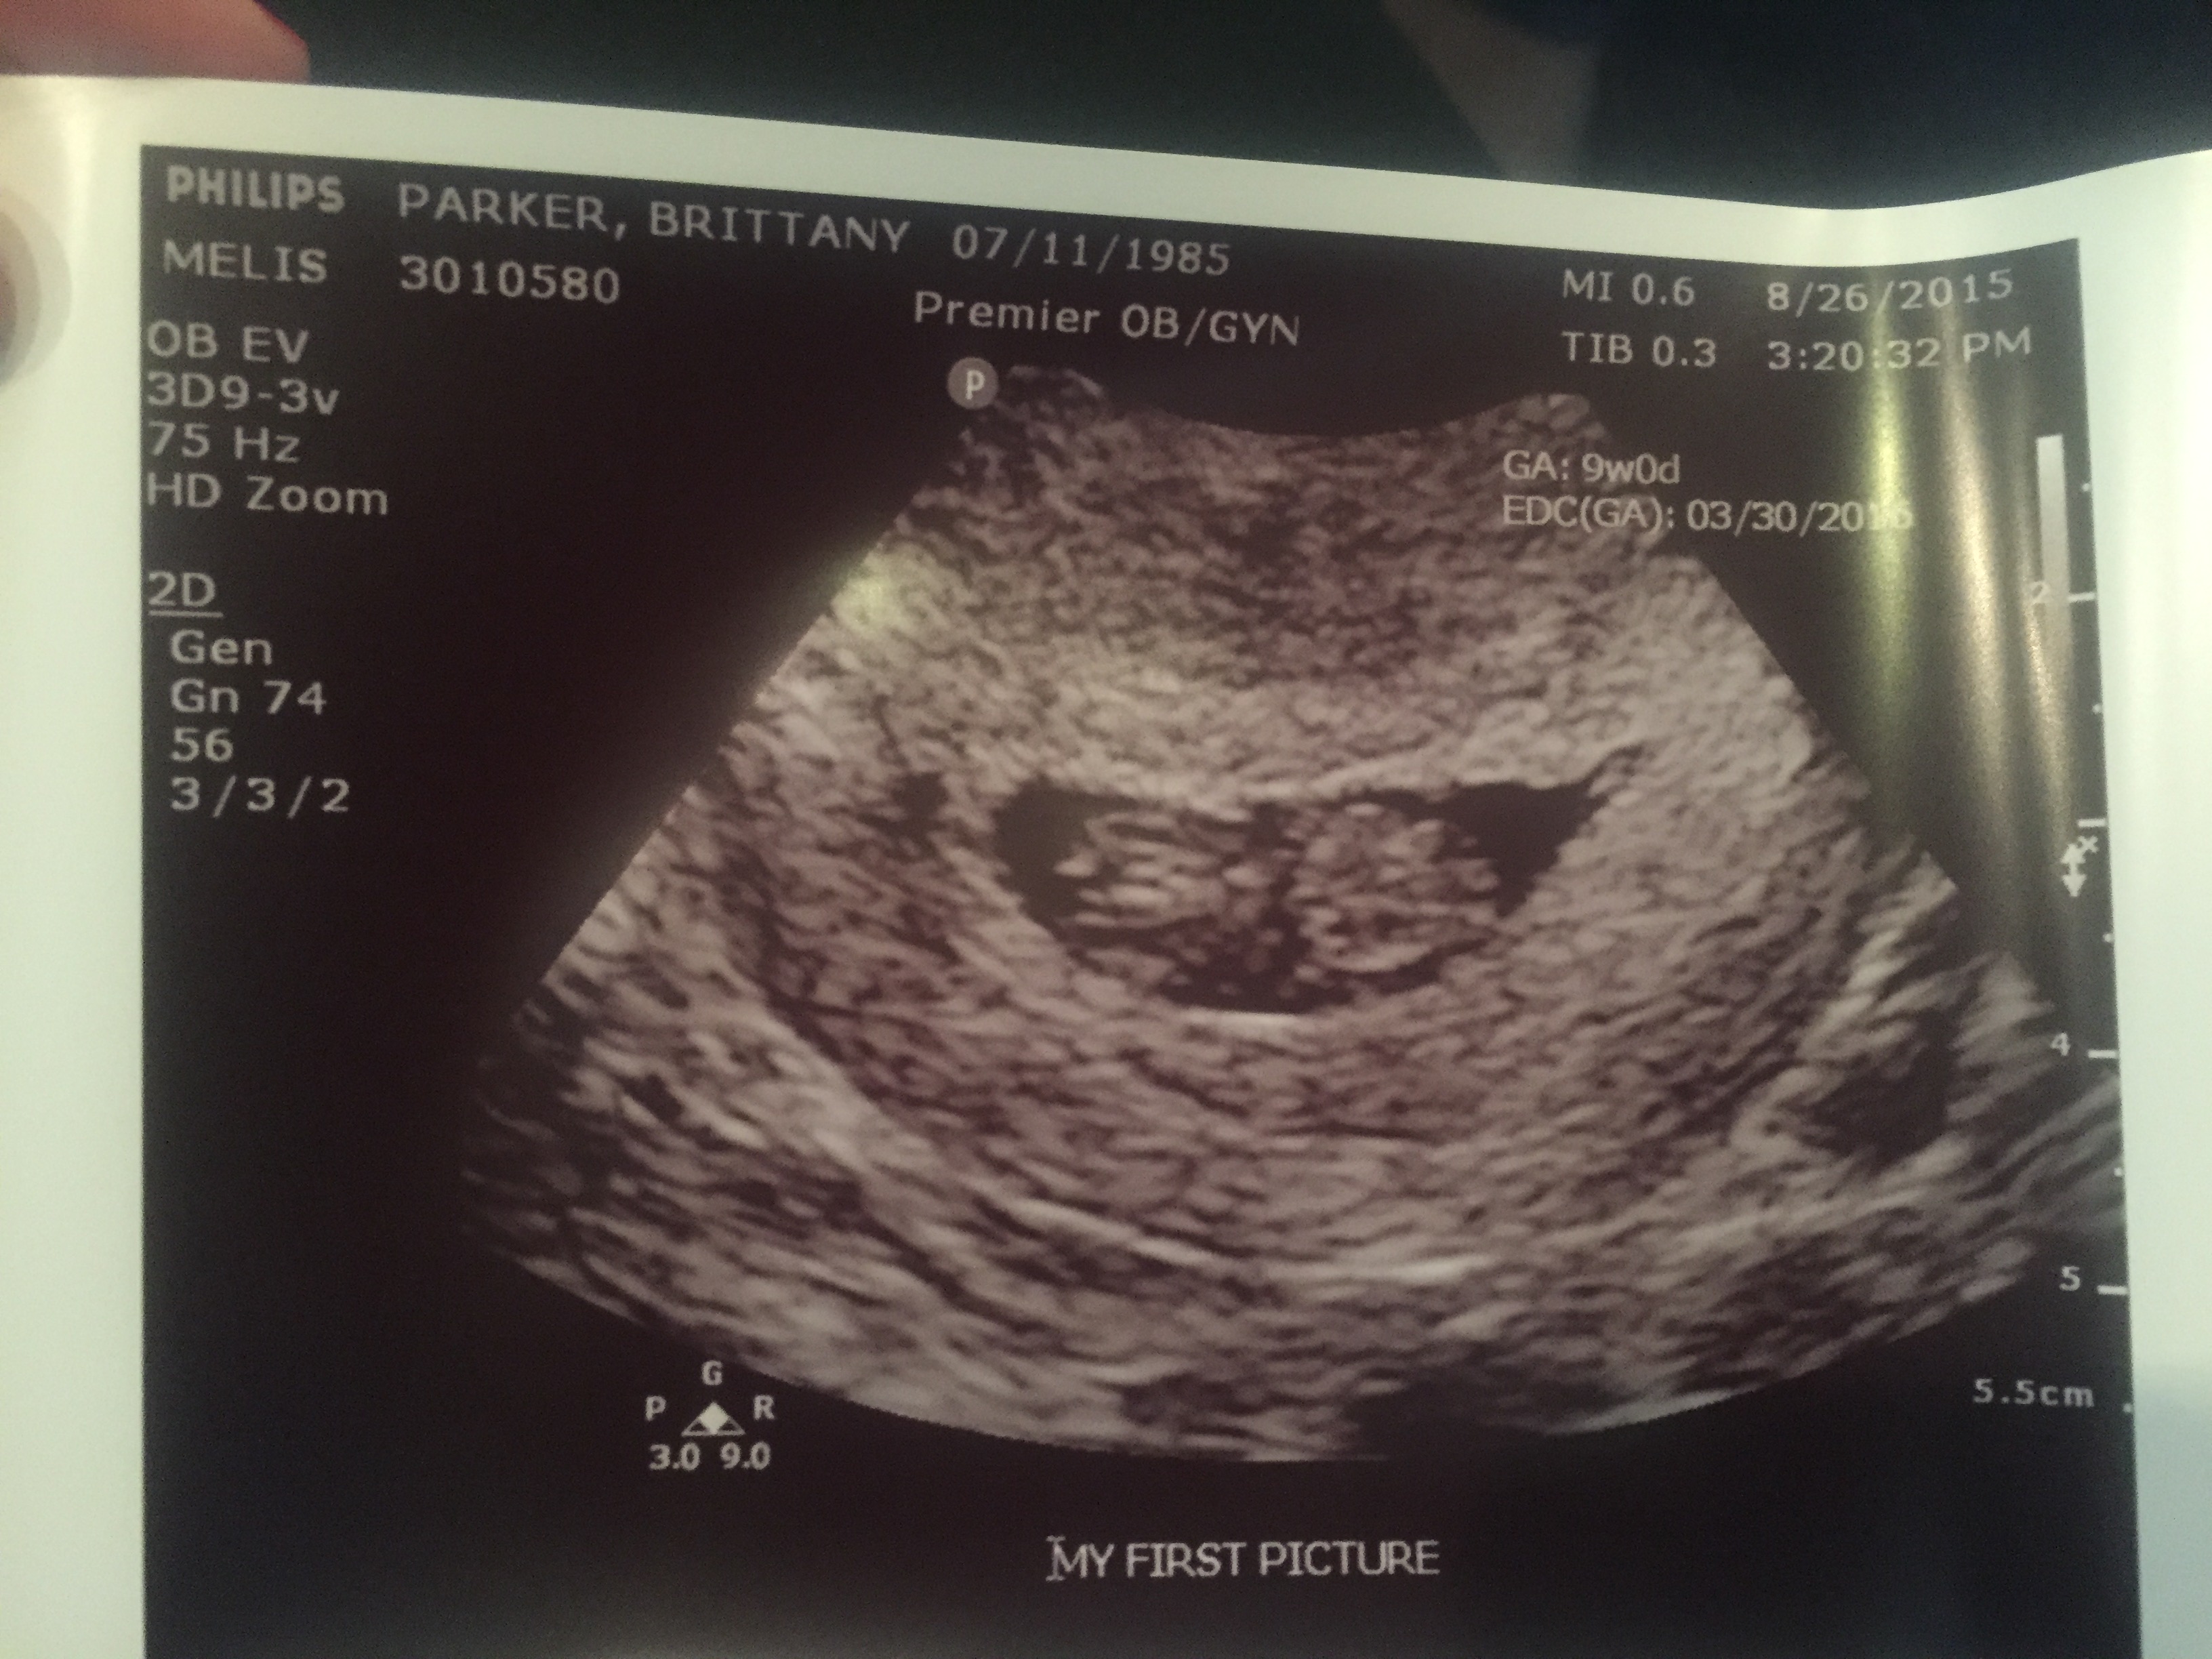

Had our first ultrasound today. Baby measured one day ahead, so exactly 9 weeks. My new edd is March 31st. Heart beat was 189 BPM. We got to see and hear its little heart beating!